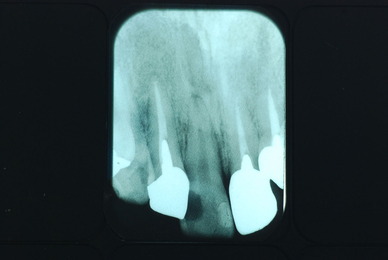

歯をいじられ体も心もボロボロになった患者さんからの手紙です。マスコミや権威などがいかにいい加減かわかります。歯は触らないほうがよろしいのです。

そもそも歯を触り何らかの金属やセラミックを入れる行為そのものが医学的には傷害処置ですから、なるべく避けるべき物なのです。